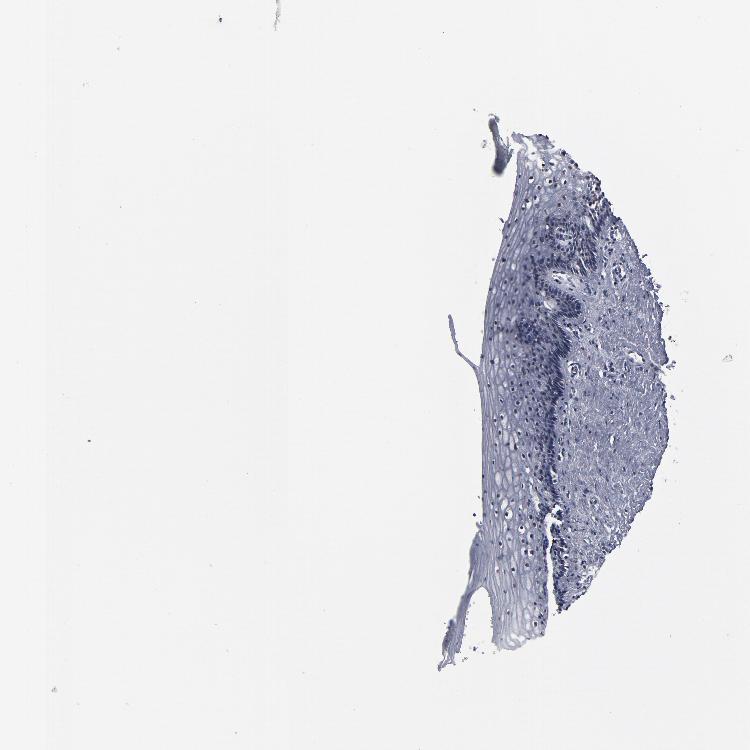

VAGINA - Antibody stainingi

Antibody staining in the annotated cell types in the current human tissue is reported as not detected, low, medium, or high, based on conventional immunohistochemistry profiling in selected tissues. This score is based on the combination of the staining intensity and fraction of stained cells.

Each image is clickable and will lead to virtual microscopy that enables deeper exploration of all samples and also displays staining intensity scores, fraction scores and subcellular localization as well as patient and tissue information for each sample.

Antibody HPA002697

Squamous epithelial cells Not detected